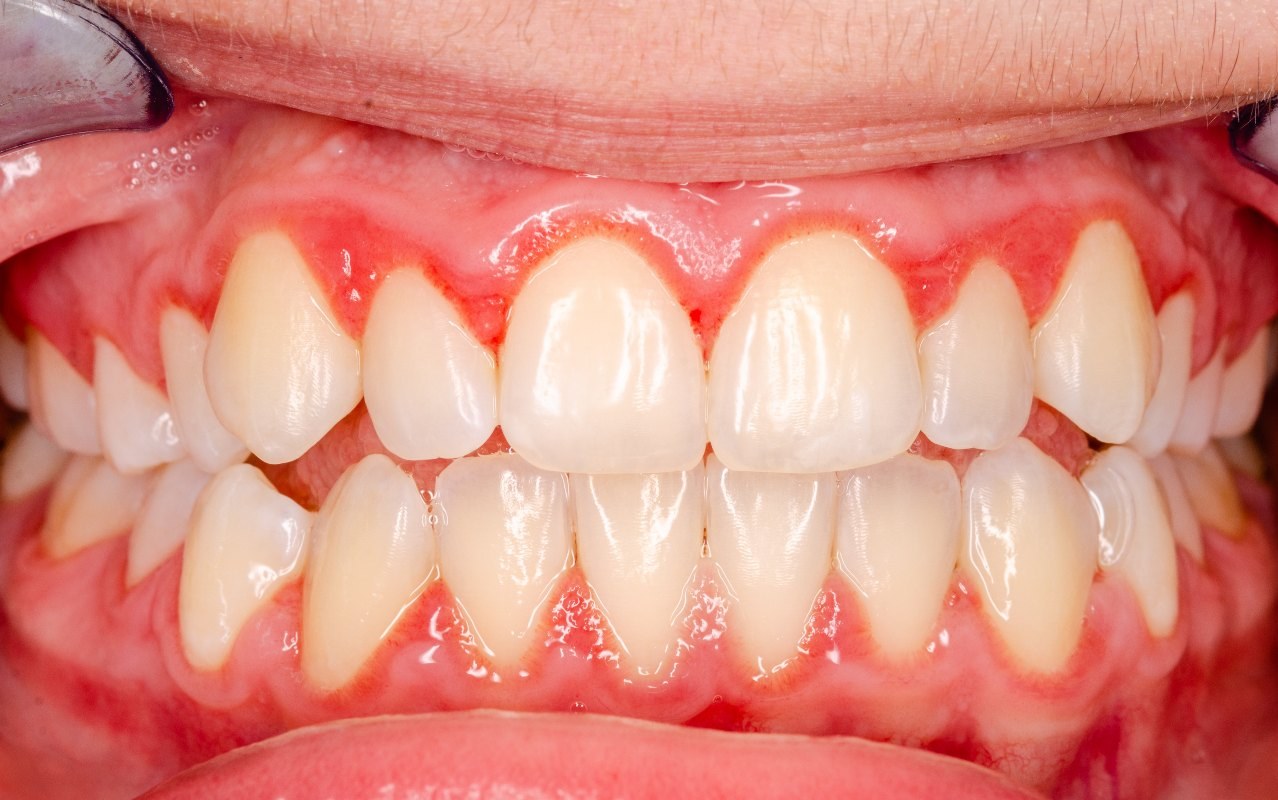

gingivitis

Definition: Inflammatory response resulting from the biofilm accumulation located below the gingival margin

gingival health: <10%, localized gingivitis: 10%-30%, and generalized gingivitis: >30%

JE at CEJ; 3mm or greater; reversible

warning signs of periodontitis

accumulation of plaque biofilm and calculus

redness (erythema) and swelling (edema)

gingival bleeding

suppuration (pus)

periodontal pockets

clinical attachment loss and tooth mobility